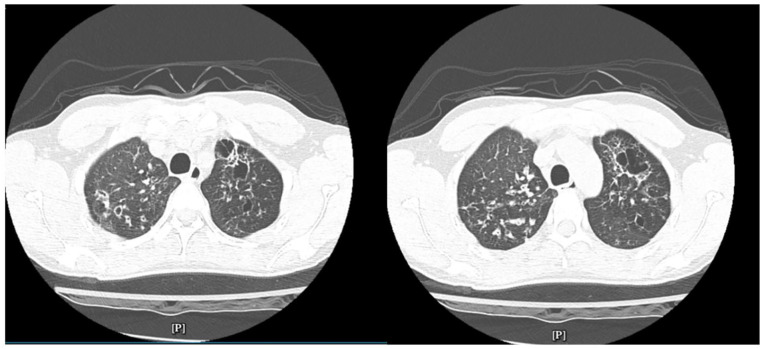

Cystic fibrosis (CF) is a genetic disorder typically diagnosed in early childhood, caused by mutations in the cystic fibrosis transmembrane conductance regulator gene, leading to thick mucus accumulation in the lungs, pancreas, and other organs. While most diagnoses occur in childhood, a growing number of cases are being identified in adulthood, presenting unique challenges for recognition and management. This case highlights a 37-year-old patient diagnosed with CF after presenting with chronic respiratory symptoms, and weight loss. Late diagnosis of CF remains rare but can delay appropriate treatment, potentially impacting long-term outcomes.